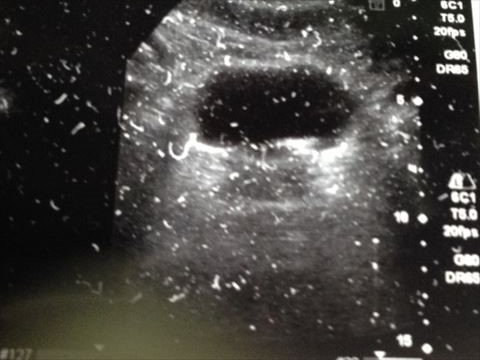

内科に行ったときエコーで見てもらいました。

腎臓の当りに結石がありました。こちらは尿管に落ちていないので痛みはないです。尿管には無かったので膀胱を見てもらいました。

膀胱に結石がありました。

エコーでは13.9ミリでした。ただ一つなのか重なっているか分からないと言われました。

おそらく重なっているんじゃないかと。

エコーの写真を撮らせてもらいましたが綺麗に写らないんじゃないとエコーの画像を印刷してくれました。

スキャナで読み込むのは大変なのでそれをスマホで撮りました。